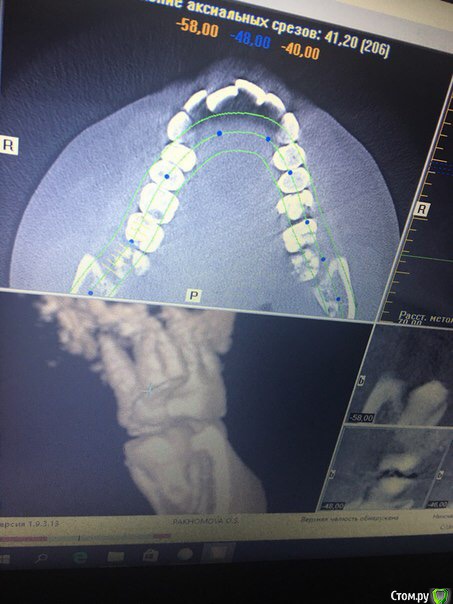

Kitty_che Опубликовано 24 августа, 2017 Поделиться Опубликовано 24 августа, 2017 (изменено) Добрый день! Обломился зуб мудрости верхний под корень,из десны не торчит,только языком можно кое как нащупать,что он там есть,не болит,но понимаю необходимость удаления,хочу только одно спросить,по фото можно понять,слишком ли сложно будет удалять зуб? Очень боюсь. Ни разу не удаляла обломанные зубы,а тут как вырос-так сразу обломился! И ещё так,что под десну. Спасибо! Изменено 24 августа, 2017 пользователем Kitty_che Ссылка на комментарий

Kitty_che Опубликовано 25 августа, 2017 Автор Поделиться Опубликовано 25 августа, 2017 Спасибо за ответ! Я просто как увидела снимок,испугалась,что корни не вместе,почему то думала,что когда корни мудрых зубов вместе как бы как один корень,то удалять проще Ссылка на комментарий

Doctor Vlad Опубликовано 26 августа, 2017 Поделиться Опубликовано 26 августа, 2017 Спасибо за ответ! Я просто как увидела снимок,испугалась,что корни не вместе,почему то думала,что когда корни мудрых зубов вместе как бы как один корень,то удалять прощевсе верно) но удалять придется все равно Ссылка на комментарий